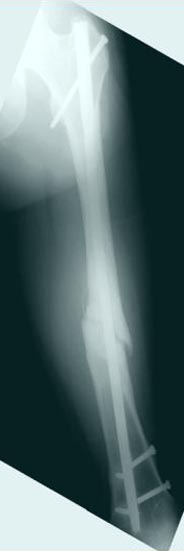

Лечение бедра - ургентное оперативное лечение антеградным с минимально рассверливанием, фиксацией с минимальным диаметром штифта и плюс irrigation and debridment и с закрытием поперечной до 10 см раны на уровне перелома в день поступления.

После трех дней начались выделения из ран которые промывалась в палате и рана постепенно закрылась в течение нескольких месяцев. Эмпирически получал 6 недельний курс антибиотика Vancomycin внутривенно.

Снимки представлены: 1 мес; 3 мес; 1 год; 2 года, предоперационные и ротационная КТ грамма